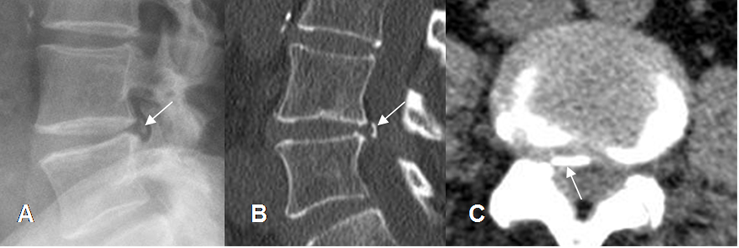

Fig 91. Hernia calcificada.

A: Rx lateral y B: TAC reconstrucción sagital. Prominencia y calcificación en la parte posterior, del disco L4-L5.

C: TAC axial. Prominencia asimétrica que borra la grasa del receso lateral y el agujero de conjunción, por hernia calcificada.

Fig 92. Hernia.

A: Rx lateral. Leve disminución del espacio L5-S1, sin otros cambios degenerativos.

B: RM axial en T2. Hernia que ocupa el receso lateral izquierdo, que desplaza y comprime las raíces.